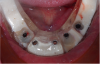

Fig. 9 through Fig. 11 The implant shifted slightly to mesial to avoid buccal concavity and bone graft. The implant was placed with a guide and a tissue punch was done, negating a flap. Figure 11 is the immediate postoperative photograph.